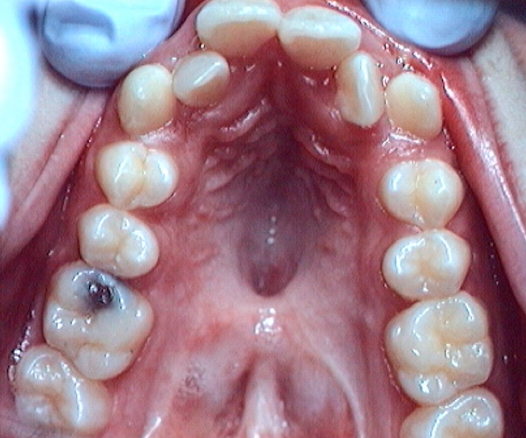

3) Dental malpositions:

Fig 4 Dental malpositions : rotations, crossbite, lack of space